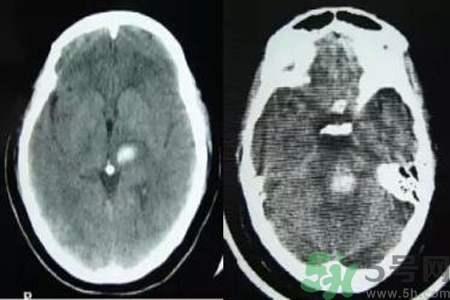

腦出血也稱腦溢血。顧名思義,腦出血是指腦實質內的血管破裂,血液溢出即為腦出血。那么腦出血的發(fā)病因素是什么?腦出血的并發(fā)癥有哪些?

因腦內小動脈壁長期受高血壓引起的張力影響,使血管壁薄弱部位形成動脈瘤,其直徑一般500μm。高血壓患者的腦內穿通動脈上形成許多微動脈瘤,多分布在基底核的紋狀動脈、腦橋、大腦白質和小腦中直徑在100~300μm的動脈上。這種動脈瘤是在血管壁薄弱部位形成囊狀,當血壓突然升高時,這種囊性血管容易破裂造成腦出血。